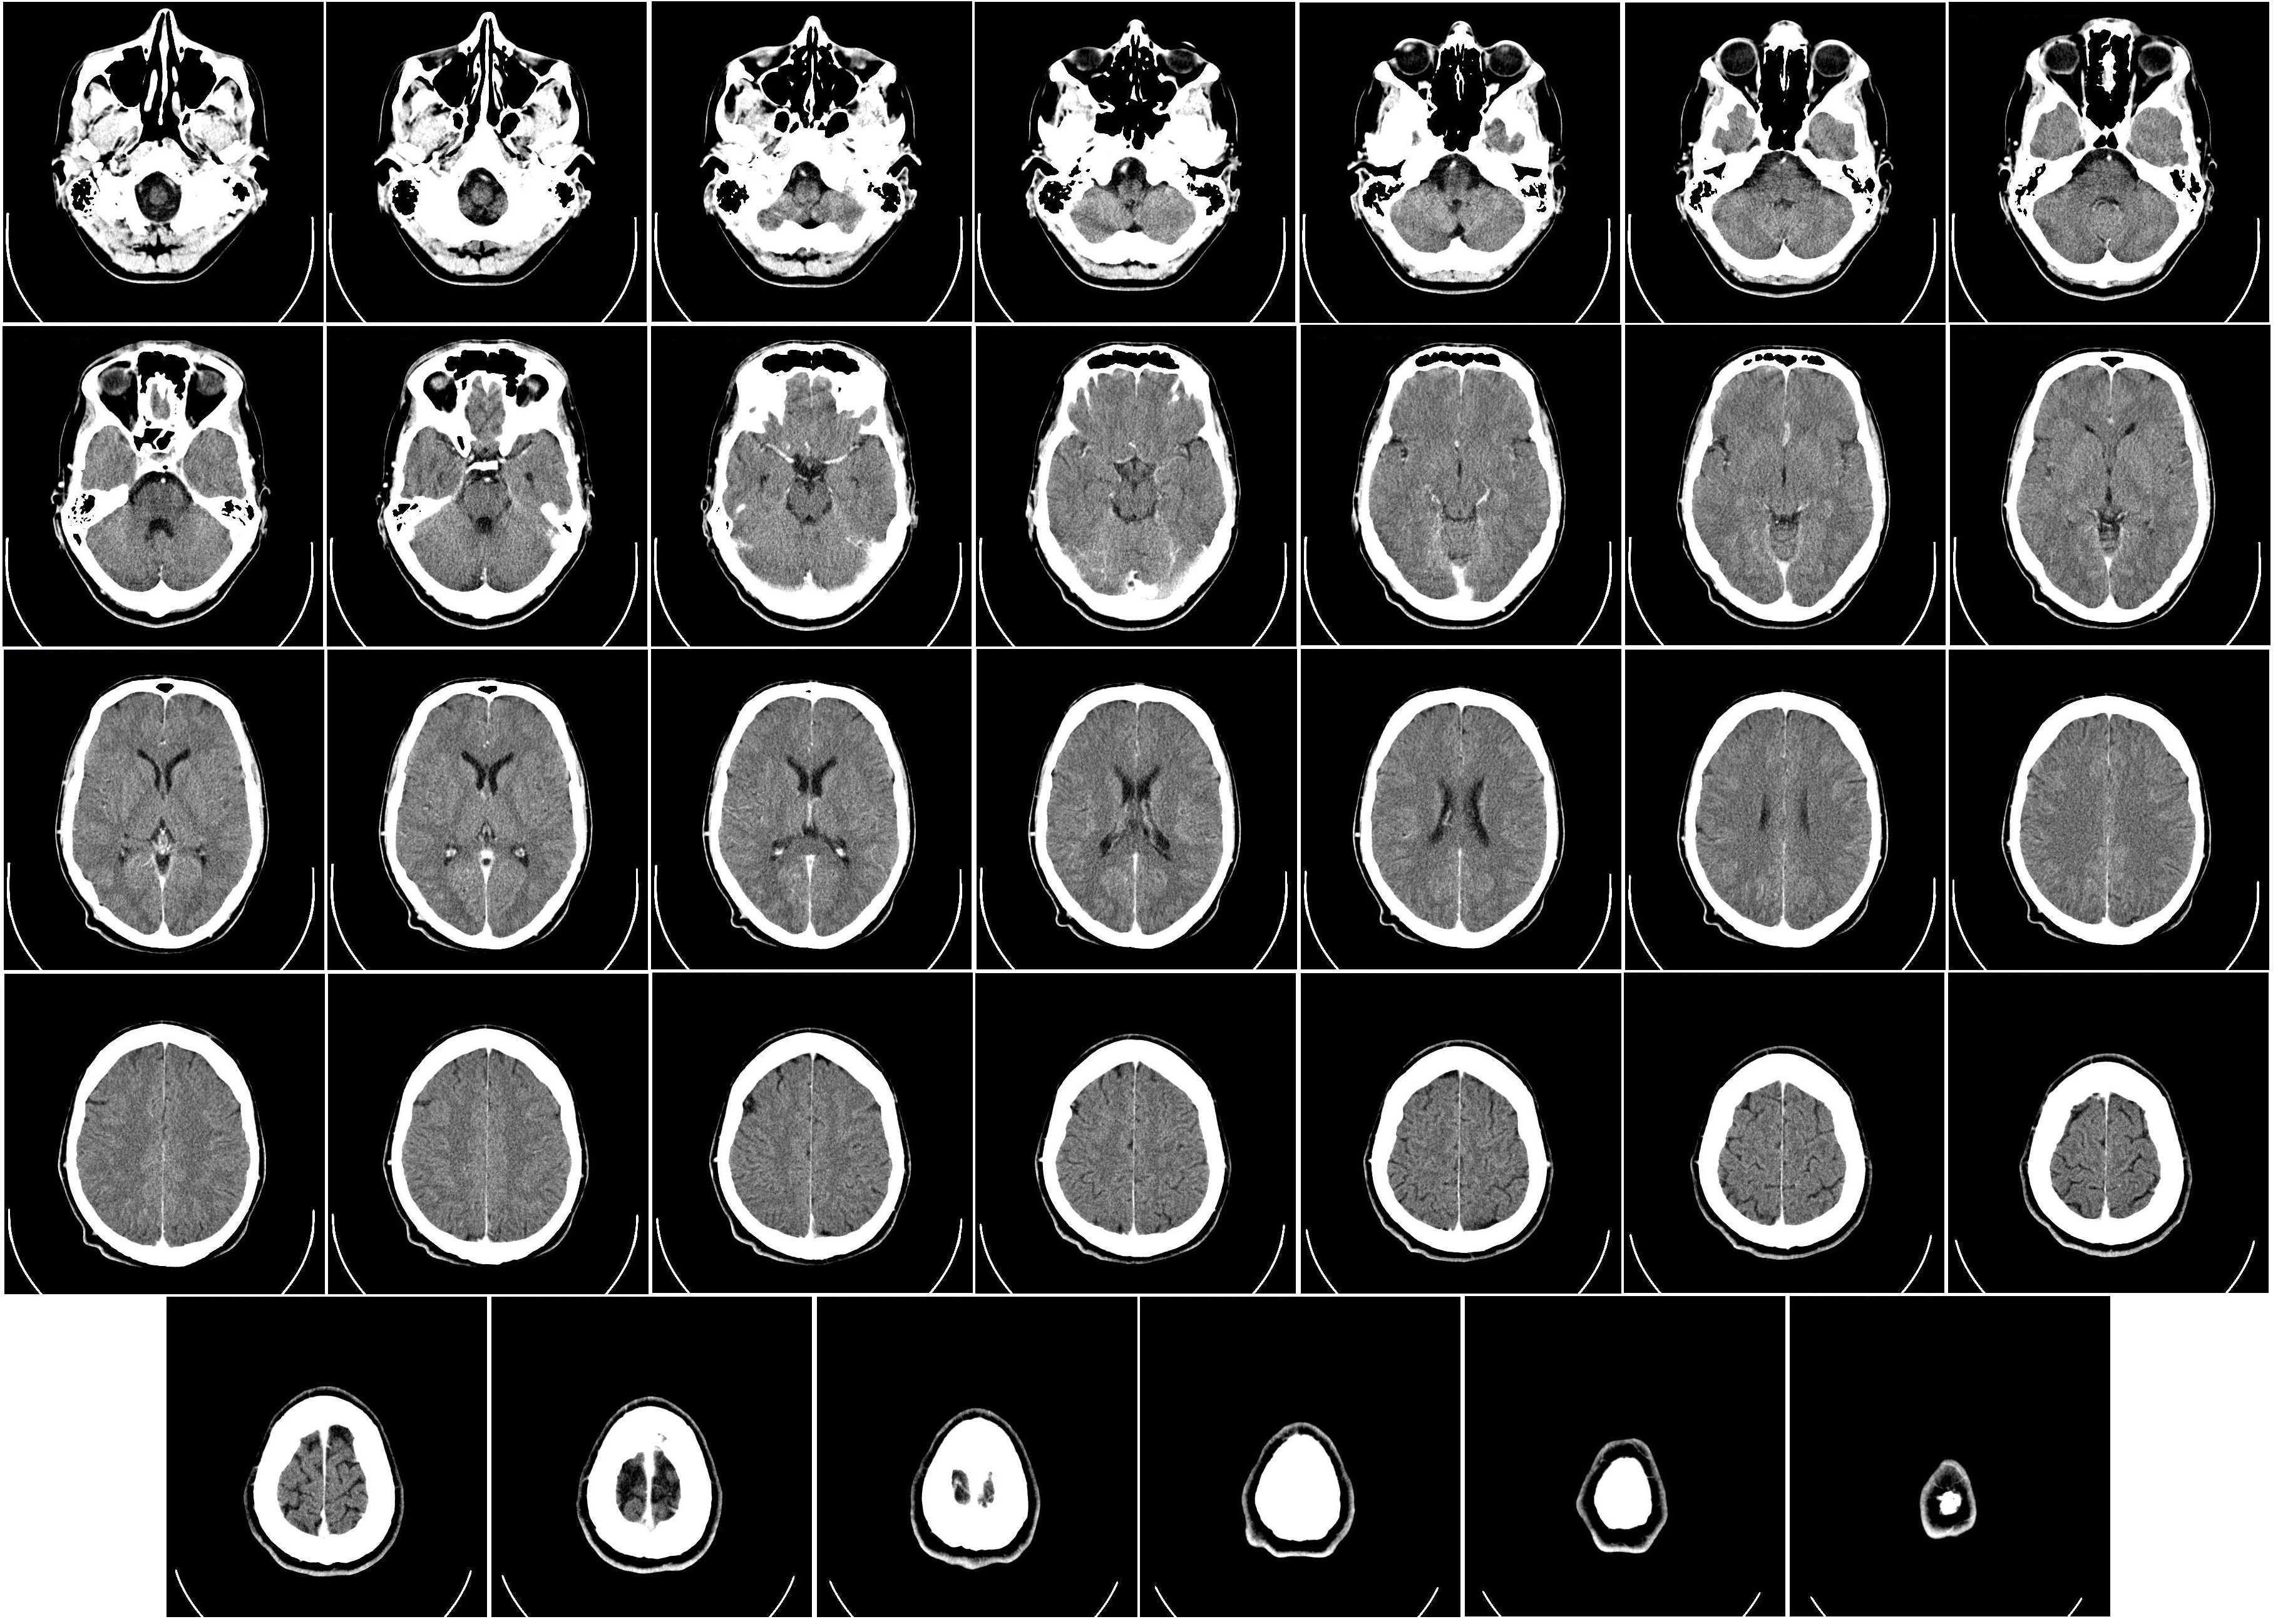

通过先进的算法和技术,我们在 2.0 版本中实现了 PT(正电子发射断层扫描)和 CT(计算机断层扫描)图像的无缝融合。这项突破性技术将为医生提供更全面、 更立体的患者图像,并且2.0 版本的图像融合带来了更高的分辨率和更丰富的图像细节。医生能够更准确地识别病变、评估组织状态,提高诊断的灵敏性和特异性, 为患者制定个性化的治疗方案提供更强有力的支持。医生可以更轻松地导航和比对 PT 和 CT 图像,提高工作效率。智能化的界面设计使操作更直观。 升级你的医学影像诊断体验,与 PT CT 图像融合 2.0 版本一同开启医学影像新时代。提升准确性,优化工作流程,为患者提供更全面的医疗服务。